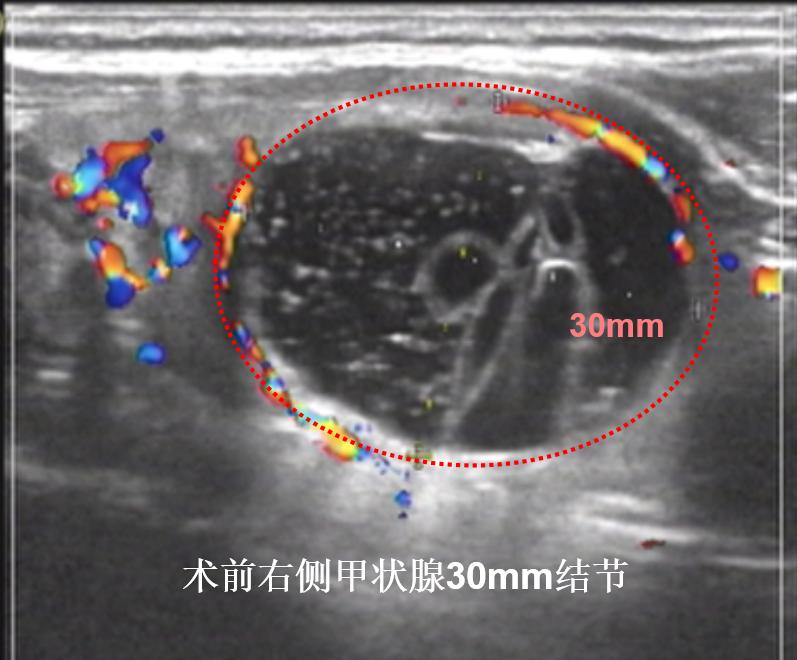

病例①:甲状腺右叶3cm结节消融前后对照,术后体表已触及不到肿物

微创消融前后超声对比,体积缩小93%